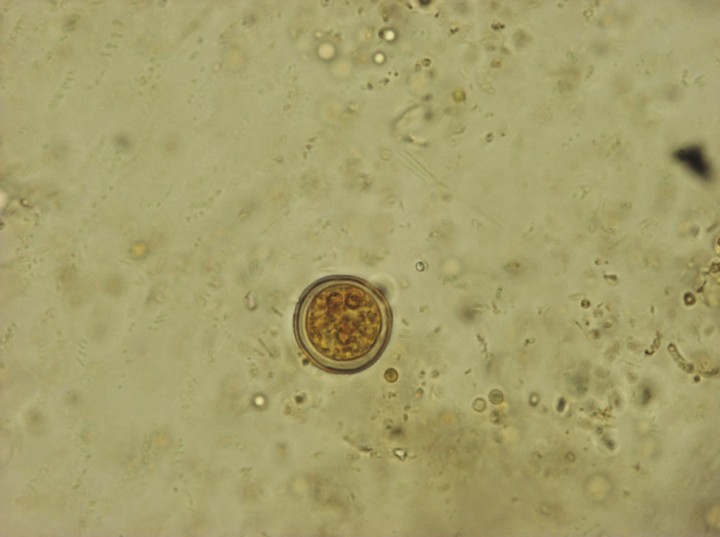

Se encontraron huevos de oxiúridos (Fig. 9) en las cuatro especies de tortugas, pero la ausencia de caracteres diferenciales no permite identificar la especie a la que pertenecen. No obstante, en algunos individuos de T. graeca se encontraron también algunas larvas y adultos expulsados de forma espontánea, que han podido ser identificados como Tachigonetria sp. Respecto a los ascáridos, solo se han encontrado en T. graeca y T. hermanni. Las características de los huevos no permiten una identificación más específica (Fig. 10), pero los adultos expulsados de forma espontánea en algunos individuos de T. graeca han sido identificados como Angusticaecum holopterum.

<p>Imagen de huevo de ascárido (Lugol, 100 x).</p>

Figura 10

Imagen de huevo de ascárido (Lugol, 100 x).

Respecto a los nematodos, en la mayoría de las muestras la identificación se realizó por la morfología de los huevos, que presentan características similares en las distintas especies de cada grupo y es relativamente fácil identificar si pertenecen a oxiúridos o a ascáridos. Los de los oxiúridos suelen ser elipsoides aplanados unilateralmente (asimétricos)[ Bouamer S, Morand S, Bourgat R. Redescription of Mehdiella microstoma and description of Mehdiella petterae sp. N., with a new definition of the genus Mehdiella Seurat, 1918 (Nematoda: Pharyngodonidae). Folia Parasitol, 2001a; 48: 132-138. [PubMed] , Bouamer S, Morand S, Bourgat R. Oxyuroids of Palearctic Testudinidae – new definition for Alaeruis Saeurat, 1918 (Nematoda: Pharyngodonidae) and redescription of Alaeuris numidica (Seurat, 1918). J Parasitol, 2001b; 87: 128-133. [PubMed] , Bouamer S, Morand S, Kara M. Redescription of four species of Mehdiella from Testudinidae, with a key to the species and discussion on the relationships among the species of this genus. Parasite, 2003; 10: 333-342. [PubMed] , Mehlhorn H, Düwel D, Raether W. Parásitos de reptiles y anfibios en: Atlas de Parasitología Veterinaria. Grass ediciones. Barcelona, 1992; 394- 406. ] (Fig. 9) y los de los ascáridos, esféricos u ovoides y de cáscara gruesa[ Bouamer S, Morand S, Bourgat R. Redescription of Mehdiella microstoma and description of Mehdiella petterae sp. N., with a new definition of the genus Mehdiella Seurat, 1918 (Nematoda: Pharyngodonidae). Folia Parasitol, 2001a; 48: 132-138. [PubMed] , Bouamer S, Morand S, Bourgat R. Oxyuroids of Palearctic Testudinidae – new definition for Alaeruis Saeurat, 1918 (Nematoda: Pharyngodonidae) and redescription of Alaeuris numidica (Seurat, 1918). J Parasitol, 2001b; 87: 128-133. [PubMed] , Bouamer S, Morand S, Kara M. Redescription of four species of Mehdiella from Testudinidae, with a key to the species and discussion on the relationships among the species of this genus. Parasite, 2003; 10: 333-342. [PubMed] , Mehlhorn H, Düwel D, Raether W. Parásitos de reptiles y anfibios en: Atlas de Parasitología Veterinaria. Grass ediciones. Barcelona, 1992; 394- 406. ] (Fig. 10). La alta prevalencia encontrada en nuestro estudio para los oxiúridos (71,4 % global) coincide con otros estudios realizados.[ Panini R, Menettii C, Mancianti F. Coprological survey in pet reptiles in Italy. Vet Rec, 2011; 169, 207. [PubMed] , Pasmans F, Blahak S, Martel A, Pantchev N. Introducing reptiles into a captive collection: The role of the veterinarian. Vet J, 2008; 175, 53–68. [PubMed] , Traversa D, Capelli G, Iorio R, et al. Epidemiology and biology of nematofauna affecting Testudo hermanni, Testudo graeca and Testudo marginata in Italy. J Parasitol Res, 2005; 98: 14–20. , Rataj AV, Lindtner-Knific R, Vlahovic K, Mavri U, Dovc A. Parasites in pet reptiles. Acta Vet Scand, 2011; 53, 33. [PMC] , Hedley K, Eatwell D, Shaw J. Gastrointestinal parasitic burdens in UK tortoises: a survey of tortoise owners and potential risk factors. Vet Rec, 2013; 173: 525. [PubMed] , McGuire JL, Miller EA, Norton TM, et al. Intestinal parasites of the gopher tortoise (Gopherus Polyphemus) from eight populations in Georgia. J Parasitol Res, 2013; 112: 4205-4210. [PubMed] ] Asimismo, el porcentaje de infestaciones concomitantes con oxiúridos y ascáridos, que asciende a un 44,64 % (50/112) (Tabla 1), es considerable, lo cual es relativamente común.[ Schneller P, Pantchev N. Parasitology in Snakes, Lizards and Chelonians. Ed Chimaira, Frankfurt am Main, 2008: 90- 172. ]